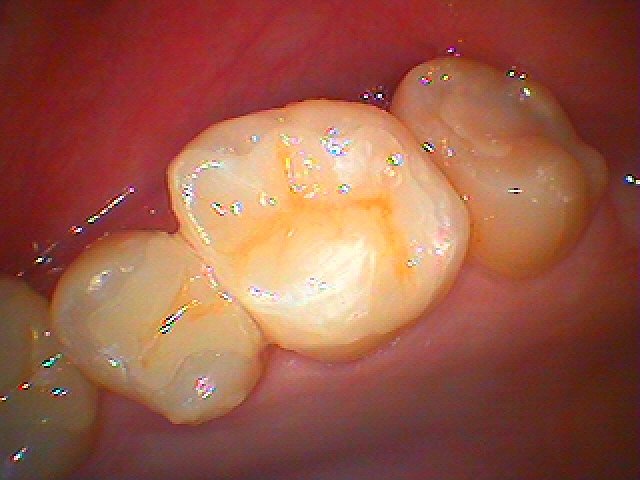

銀歯をすべてセラミックへやり変えていきます セラミックを用いた臨床例 審美治療|お知らせ |広島市安佐南区の歯科医院 銀歯をすべてセラミックへやり変えていきます セラミックを用いた臨床例 審美治療 トップ お知らせ・ブログ お知らせ 銀歯をすべてセラミックへやり変えていきます セラミックを用いた臨床例 審美治療 銀歯をすべてセラミックへやり変えていきます セラミックを用いた臨床例 審美治療 左上の6番部になります この銀歯を外して虫歯治療を行っていきます 中はこのようになっていました 近心部の虫歯を除去していきました CR樹脂にて覆罩を行っています セレックセラミックにて修復しています 銀歯が外れたとのこと わずかに虫歯が存在していました セレックセラミックにて修復しています 綺麗に仕上がりました Web診療予約 初めての方へ 選ばれ続ける理由 院内設備について 歯が痛いしみる一般歯科 歯がぐらぐらする歯周病 健康な歯を保ちたい予防歯科 子供の虫歯予防をしたい小児歯科 銀歯をセラミックに審美歯科 白い歯を目指しませんか?ホワイトニング 矯正専門医がいるので安心矯正歯科 抜けた歯を補いたいインプラント・入れ歯 医院案内 スタッフ紹介 メリィハウス歯科クリニックオフィシャルホームページ ラベンダー歯科クリニックオフィシャルホームページ お知らせ・ブログ ホーム 診療科目 一般歯科 歯周病治療 予防治療 小児歯科 審美治療 ホワイトニング 矯正歯科 入れ歯・インプラント マウスピース矯正 初めての方へ 院長・スタッフ 設備紹介 医院案内・アクセス メニューを閉じる